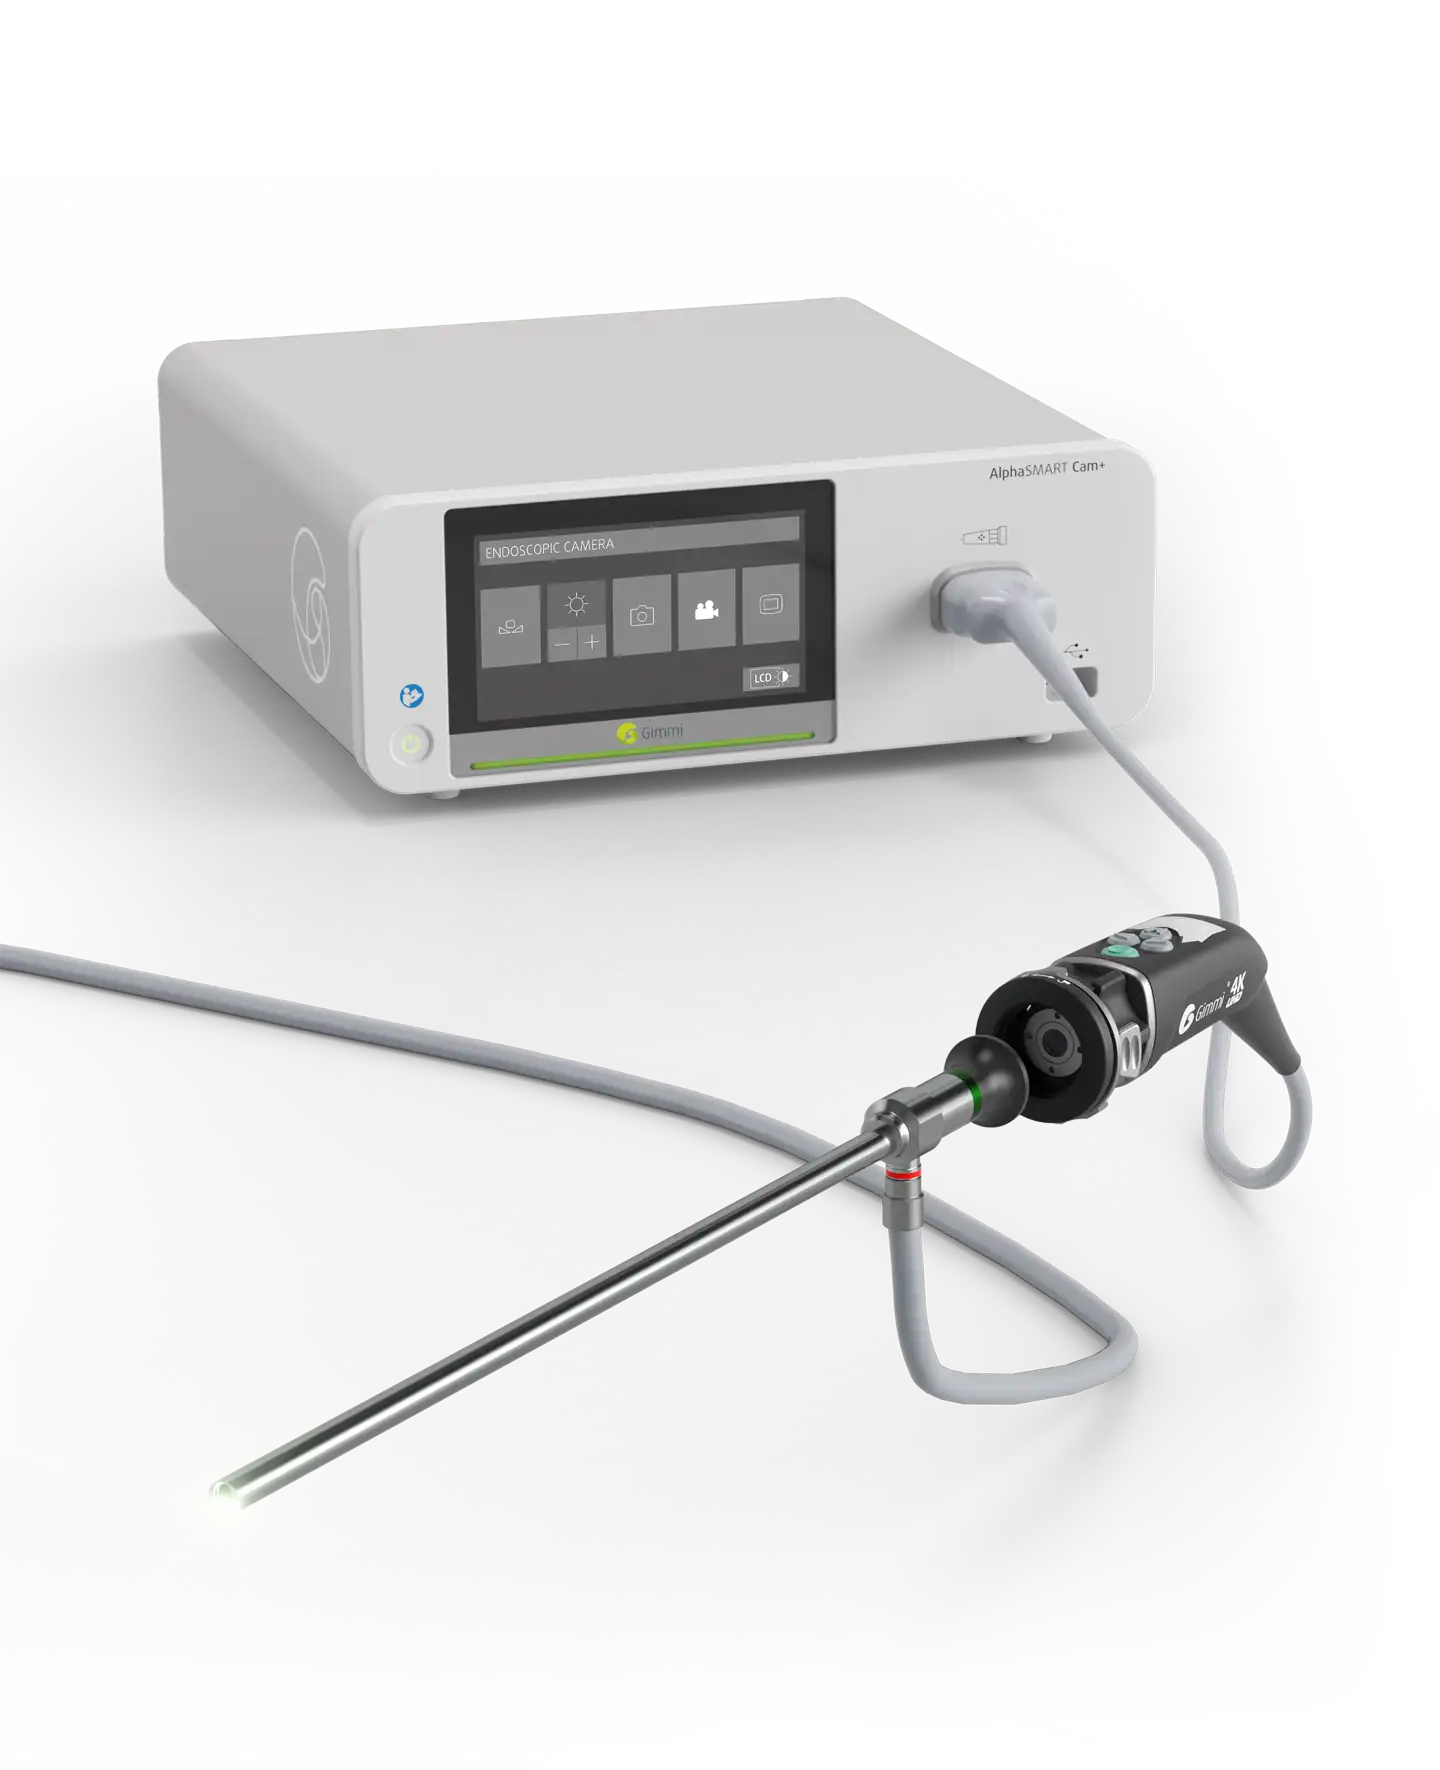

AlphaSMART Cam+ – Telecamera endoscopica e teste telecamera

L'occhio perfetto – AlphaSMART Cam+ e teste per telecamera

Excellent image quality is what makes an endoscopy solution the right instrument. The camera in the AlphaSMART series, however, is perfect not only in terms of image quality. It also offers high-quality features.

Progettata per le esigenze della moderna chirurgia mininvasiva, AlphaSMART Cam+ offre immagini ad alte prestazioni in un design compatto e intuitivo. L’interfaccia semplificata riduce i tempi di configurazione e la compatibilità con diverse modalità di imaging garantisce flessibilità per molte specialità.

AlphaSMART Cam+ è più di un controller per telecamere: è la base di un flusso di lavoro di imaging flessibile ed efficiente. Grazie alle opzioni modulari della testa della telecamera e alla connettività intelligente, consente alle équipe chirurgiche di ottenere chiarezza, controllo e sicurezza.